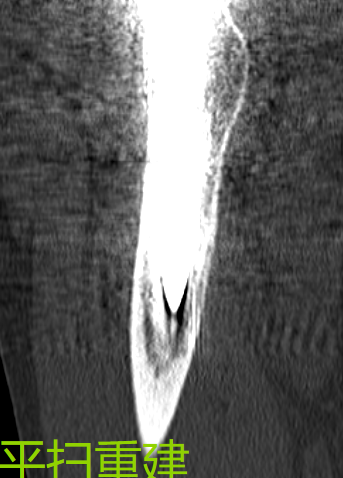

对比图像清晰显示:3月11日常规平扫图像中,金属伪影严重,结构显示不清;而3月12日采用MAR技术扫描后,无论是横断面还是冠状位重建图像,金属伪影均基本消除,解剖结构清晰可见,为临床精准评估和假体设计提供了可靠依据。

注:以下图片展示了常规平扫与MAR技术扫描的对比效果,清晰呈现金属伪影消除技术的临床价值。

普遍矢状重建(金属伪影较重)